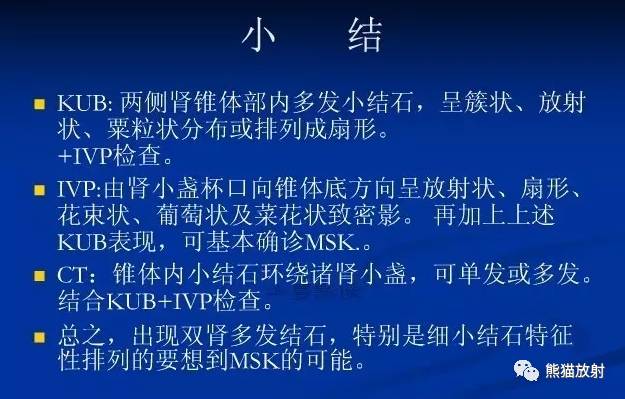

Findings 影像表现

CT urogram (2017): Noncontrast images demonstrate multiple bilateral nonobstructing renal calculi, the largest measuring 6 mm in the right kidney. Some of the calcifications could represent nephrocalcinosis — for example, those in the upper pole of the right kidney. The kidneys show symmetric enhancement without suspicious renal mass. Multiple bilateral exophytic simple renal cysts are noted, the largest in the midpole of the right kidney measuring 3.6 x 4.3 cm. There are additional subcentimeter low-attenuation lesions that are too small to characterize. There is a “paintbrush sign” appearance to the renal medullae in keeping with a history of medullary sponge kidney. There is mild bladder wall thickening and trabeculation that may be related to chronic outlet obstruction. Further evaluation is deferred to cystoscopy.

CTU:CT平扫可见双肾多发非梗阻性肾结石,右肾最大者直径约6mm,其中一些钙化可能代表肾结石,例如,右肾上极的那些。肾脏对称性强化,未见可疑肾肿物。双肾可见多发单纯性肾囊肿,大者位于右肾中部,大小约3.6 x 4.3 cm;另可见不足1cm的低密度灶,其太小而不能显示。肾髓质表现为“毛刷征”,符合髓质海绵肾。膀胱壁轻度增厚并小梁形成,与慢性流出道梗阻有关。进一步评估需膀胱镜检查。

IVP (2005): Preliminary scout images demonstrate a cluster of at least three radiopaque stones in the upper pole of the right kidney; the largest two stones in this cluster each measure 6 mm in diameter. In addition, there are probable clusters of smaller stones in the interpolar right kidney and right lower pole. Following the uneventful intravenous administration of 150 mL of nonionic contrast material, prompt nephrograms develop, which show the kidneys to be normal in size, shape, appearance, and internal architecture. There is diffuse bilateral tubular ectasia. Contrast is excreted promptly into otherwise normal-appearing pyelocalyceal systems. The calculi are no longer seen and likey reside in dilated tubules. The ureters are normal in course, caliber, and appearance. The urinary bladder has a mildly trabeculated appearance. There are two small urinary bladder diverticula: one of the bladder dome and one arising from the left lateral bladder wall. No filling defects are seen.

IVP:预扫定位像可见右肾上极至少3个阳性结石,簇状分布,最大的两个直径约6mm。另右肾中部及下极可见成簇的小结石。静脉注射非离子型对比剂150ml,立即摄片,可见肾脏大小、形态、表现及内部结构正常,可见弥漫性双侧肾小管扩张,造影剂进入正常的肾盂肾盏系统。钙化并未显示,可能在扩张的肾小管内。输尿管走行、直径及表现正常,膀胱轻度小梁形成,可见两个小膀胱憩室,一个位于膀胱顶壁,一个位于左侧壁;未见充盈缺损。

Diagnosis: Medullary sponge kidney

最后诊断:髓质海绵肾

Imaging features 影像表现

Radiography: May see medullary nephrocalcinosis (calcifications within medulla) or urolithiasis.

平片:可见肾髓质钙质沉着(髓质内钙化)或尿路结石

IVP:

IVP:

CT:

CT:

鉴别诊断:

1)肾结石:位于肾盂或肾小盏内,增强后排泌的造影剂常把结石掩盖,较大的结石常使其以远的肾盏发生梗阻性积水。

2)肾结核:一般常单侧发生,肾实质内可见单发或多发大小不等、形态不一的囊腔,囊壁有钙化斑,局部肾盏可见不规则的破坏或造影剂充盈不佳,常并发有肾盏、肾盂积水。

3)肾乳头坏死:愈合期表现为集合小管内或周围弥散性钙盐沉积,钙化较海绵肾更广泛。